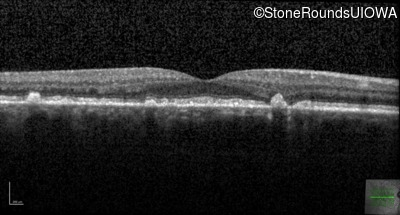

Optical Coherence Tomography - Left - 20/32 sc

Exemplar / OCT Stack